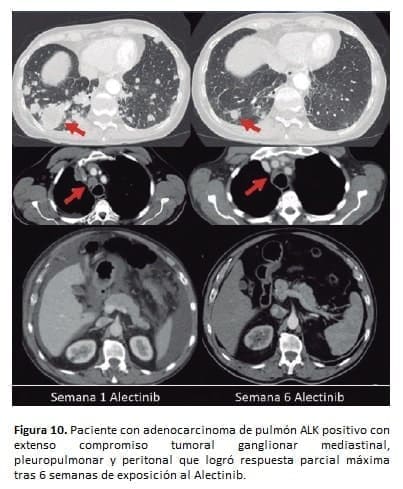

La Figura 10 ilustra la rápida respuesta reflejo del uso del alectinib en un paciente con extenso compromiso visceral y ganglionar por un adenocarcinoma de pulmón ALK positivo.